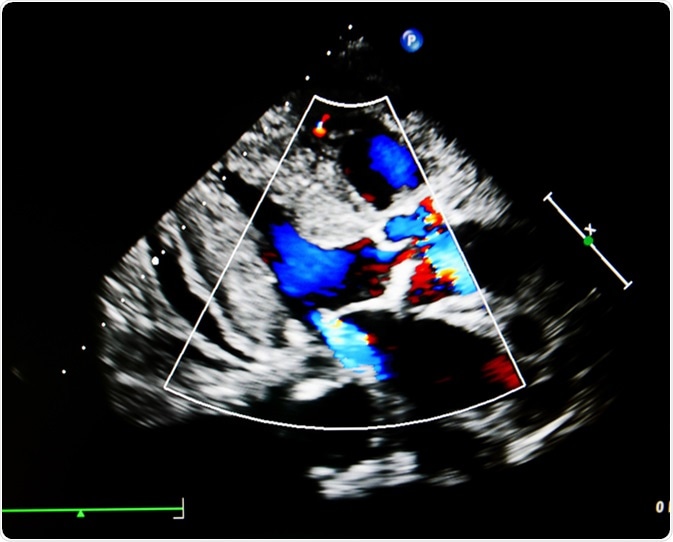

Flow color mode show jet from aortic and mitral valve regurgitation. Image Credit: Ling Stock / Shutterstock

Mitral regurgitation (MR) is also called mitral insufficiency, and is a condition in which the valve allows blood to leak back into the left atrium when the ventricle contracts, instead of holding tight so that ventricular contractions can force blood out of the heart into the aorta, the great vessels that supplies branches to the various parts of the body except the lungs.